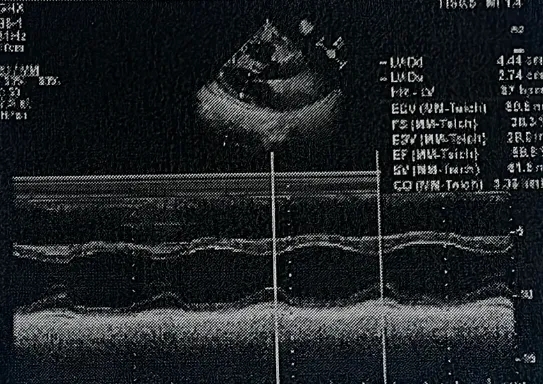

出院前超声复查

-

超声所见:房间隔中部可见封堵器强回声,封堵后房间隔中部可见封堵器强回声,位置固定,CDFI:目前房水平未见明显过隔血流信号。右室轻大,CDFI:收缩期,二尖瓣房侧可见少量反流信号;收缩期,三尖瓣房侧可见少量反流信号。

超声提示:房间隔缺损封堵术后房水平未见残余分流、右室轻大、二尖瓣少量反流、三尖瓣少量反流。